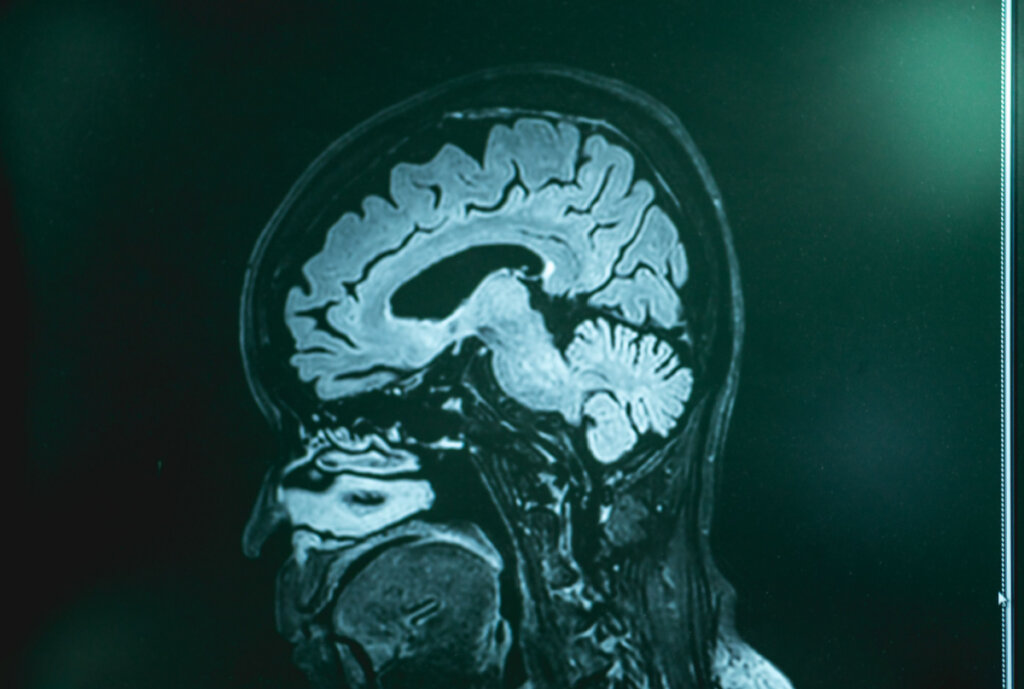

Malgré l’ignorance de cause à effet qui existe actuellement concernant ce type particulier de démence, diverses hypothèses sont envisagées, certaines avec plus de succès. Grâce aux procédures de neuroimagerie, une certaine atrophie peut être observée chez ces patients, c’est-à-dire un “rétrécissement” de certaines zones du cortex, en particulier dans le cortex temporal et frontal.